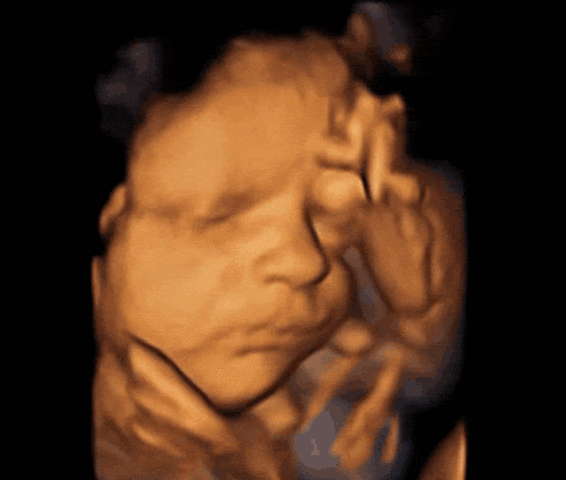

La longitud del embrión es de 3 a 4 cm y su peso unos 5g, tiene cada vez más forma humana y se distinguen los brazos y los antebrazos, las manos se abren y se cierran y están a la altura de la boca, la cara esta más redondeada, los ojos permanecen cerrados y la boca se abre y se cierra, la mineralización de los huesos progresa intensamente sobre todo en el cráneo.

• Onceava semana.

Onceava semana.

La longitud del bebé es de unos 4 a 6 cm y su peso de unos 8gr.

La cabeza sigue ocupando más de la mitad de la longitud embrionaria, aparecen barbilla y cuello a medida que la cabeza se va separando del pecho, las uñas de los dedos son más visibles, los genitales externos se distinguen con claridad.